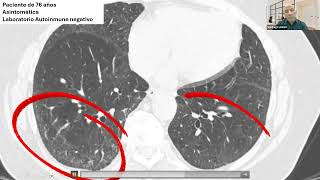

Webinar Enfermedades Intersticiales ALAT 18 Sept 2025